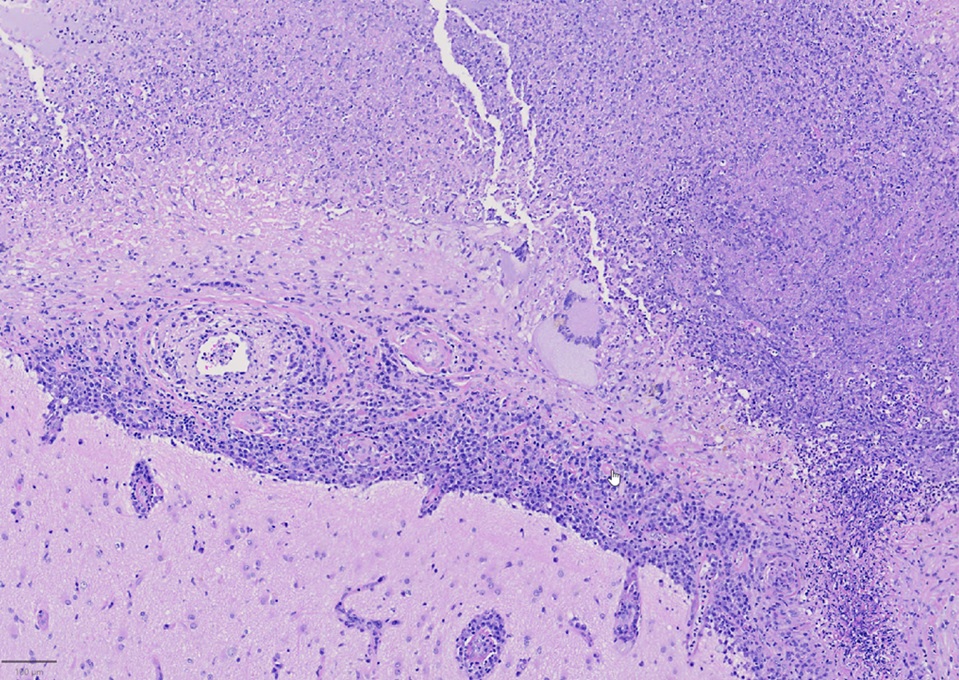

A 79-year-old right handed woman presented to a local hospital with left hemiparesis affecting her upper and lower extremities with mild left facial weakness for the last 2 weeks. She had a longstanding history of RA and had been off immune suppressant therapy for a few months due to improvement in symptoms. She had previously been on methotrexate and adalimumab in the past. She was evaluated with imaging and lumbar puncture (LP) at the time. MRI brain showed a semi-enhancing lesion over the right frontal lobe near the motor cortex with meningeal enhancement (Figure 1). CSF studies showed elevated protein at 65 and pleocytosis with WBC count of 47, 80% lymphocytes. CSF infectious panel was negative, but serum HSV-1 was positive. She reported a cold sore around this time as well. She was treated with broad spectrum antibiotics and acyclovir for 2 weeks. Infectious workup was otherwise negative. She did not have much improvement in her symptoms and was presented to our hospital 3 weeks later. Repeat CSF evaluation showed protein of 70 along with pleocytosis of 33 white blood cell (WBC), 75% lymphocytes. She received treatment with extended broad-spectrum antibiotics for 2 weeks. Rheumatological evaluation was negative for other signs of active RA. EEG showed bitemporal slowing with some quasi-periodic activity over the right temporal regions. She had some left arm shaking as well and was placed on levetiracetam for seizure prophylaxis. She did not have much improvement in her symptoms. A brain biopsy was performed which showed histopathological findings consistent with granulomatous inflammation confirming a diagnosis of RM (Figures 2-4). Labs showed highly elevated rheumatoid factor (RF) (>320) and anti-cyclinolytic citrullinated peptide (CCP) antibodies (>250). Rheumatology was consulted again and recommended high dose therapy with intravenous methylprednisolone for 5 days followed by resumption of immune modulating therapy. She developed a small right frontal ischemic stroke as a resultant of vasculitis from RM which caused exacerbation of left lower extremity weakness (Figure 5). She is kept on aspirin 81 mg daily for maintenance therapy for stroke prevention and levetiracetam for seizure prophylaxis along with daily prednisone and rituximab maintenance therapy for management of her RA / RM from rheumatology. She continues to work with physical therapy for her left hemiparesis which has shown some improvement. She sees rheumatology and neurology for continued follow up.

Figure 3. Leptomeningeal inflammation consisting of numerous plasma cells and rare giant cells with extensive necrosis.

Histopathological findings eventually determine the diagnosis. In Bathon's assessment, 17 out of 19 victims had RM diagnosed after postmortem. An open brain biopsy was used to make the diagnosis in two cases. Meninges that had swollen nodules or plaques were frequently seen during a physical examination. Rheumatoid nodules, generalized meningeal inflammation, and vasculitis were three aberrant patterns that emerged through microscopic pathological analysis. The majority of the findings (68%) were nodules, which shared histological similarities with subcutaneous rheumatoid nodules. Nodules were seen in the choroid plexus (15%) and the cerebral meninges (92%). The spinal meninges were affected in two patients. The spinal cord or brain parenchyma had no nodules. In 63% of instances, it was discovered that the leptomeninges or pachymeninges had non-specific inflammatory infiltrates with mononuclear cells, primarily plasma cells, and less commonly necrosis and multinucleated giant cells. It is unclear why invading inflammatory cells prefer the meninges—in particular, the dura—to the brain parenchyma. Although brain parenchyma is not a large component of the dura, autoimmune reactions to collagen may be a factor [1]. In 37% of instances, vasculitis was found to have affected the meninges, spinal cord parenchyma, and the brain, as seen in our patient. Lymphocytes and plasma cells were present in the infiltrates of vessel walls. According to the authors, CNS rheumatoid nodules could be regarded as unique to CNS rheumatoid illness. The presence of plasma cells may help to identify CNS rheumatoid illness from other connective tissue disorders like systemic lupus erythematosus (SLE) or Sjögren syndrome in cases of non-specific chronic inflammatory infiltration by vasculitis or meningitis. Rheumatoid nodules are the most typical autopsy findings in people with RA. It is a non-specific inflammatory infiltrate among individuals with biopsy-diagnosed conditions, perhaps as a result of insufficient tissue sample [1,5].